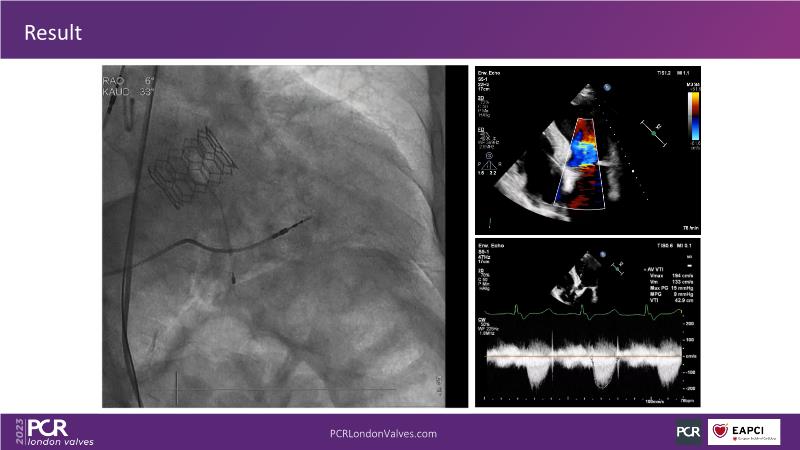

In this session, discover the key features and benefits of next-generation transcatheter heart valve technology. Gain insights into managing bicuspid and valve-in-valve interventions, and understand the procedural and clinical significance of intermediate and XL sizes in addressing unmet clinical needs.

- Learn about the next generation transcatheter heart valve technology key features, procedural and clinical benefits

- Understand the importance of predictable and precise commissural and coronary alignment for lifetime management of TAVI patients